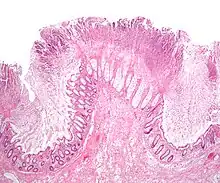

| A micrograph demonstrating cryptitis, a microscopic correlate of colitis. H&E stain. | |

An important investigation in the assessment of colitis is biopsy for histopathology. A very small piece of tissue (usually about 2mm) is removed from the bowel mucosa during endoscopy and examined under the microscope by a histopathologist. A biopsy report generally does not state the diagnosis, but should state any presence of chronic colitis, give an indication of disease activity, as well as state the presence of any epithelial damage (erosions and ulcerations).[6]

Histopathology findings generally associated with chronic colitis include:[6]

Crypt degeneration

Crypt branching and other architectural distortions

Paneth cell (pictured) or gastric metaplasia (only applies in the left colon and rectum)

Other findings include basal plasmacytosis and mucin depletion.[6] Histopathology findings generally associated with active colitis include:[6]

Neutrophilic cryptitis (neutrophils within crypt epithelium)

Crypt abscesses (luminal neutrophilic aggregates)

Gland destruction

Ulceration (seen here as absence of epithelium, and granulation tissue with many fibroblasts)